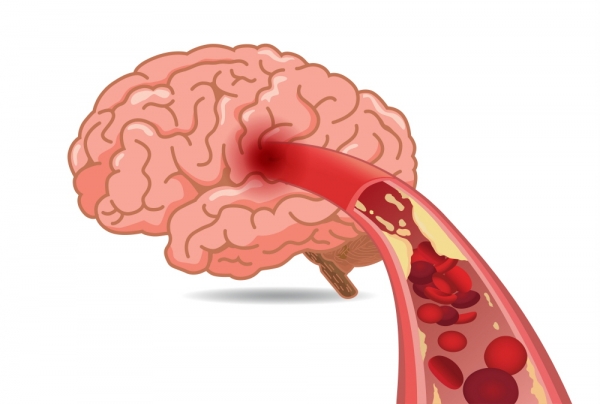

먼저, 뇌경색이 무엇인지 간단히 설명드리고자 합니다. 뇌경색은 뇌의 일부에 혈액 공급이 차단되면서 발생하는 질환입니다. 이로 인해 해당 뇌 영역이 손상되고, 다양한 증상이 나타납니다. 뇌경색은 크게 허혈성 뇌경색과 출혈성 뇌경색으로 나뉘며, 허혈성이 더 일반적입니다. 이 증상은 초기 발병 시점에 따라 치료의 효과가 크게 차이가 납니다.